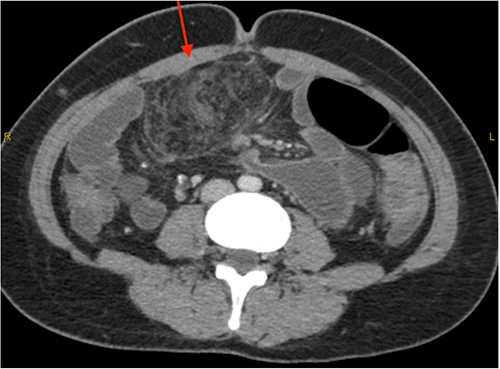

On review of imaging, we noted a CT scan from 2019 which showed swirling and stranding of omentum/mesenteric fat inferior to hepatic flexure (CC 1.8 cm, TV 2.6 cm), with suspicion of internal herniation of the omental/mesenteric fat leading to infarction (Figs 1 and 3). Management of this was unclear as this was at a private hospital in metropolitan Western Australia. A repeat CT scan during her current presentation revealed similar swirling of omentum/mesenteric fat, but with interval increase in size (CC 5.5 cm, TV 7.6 cm). There was associated small bowel dilatation and wall thickening and enhancement with no focal transition point (Figs 2 and 4).